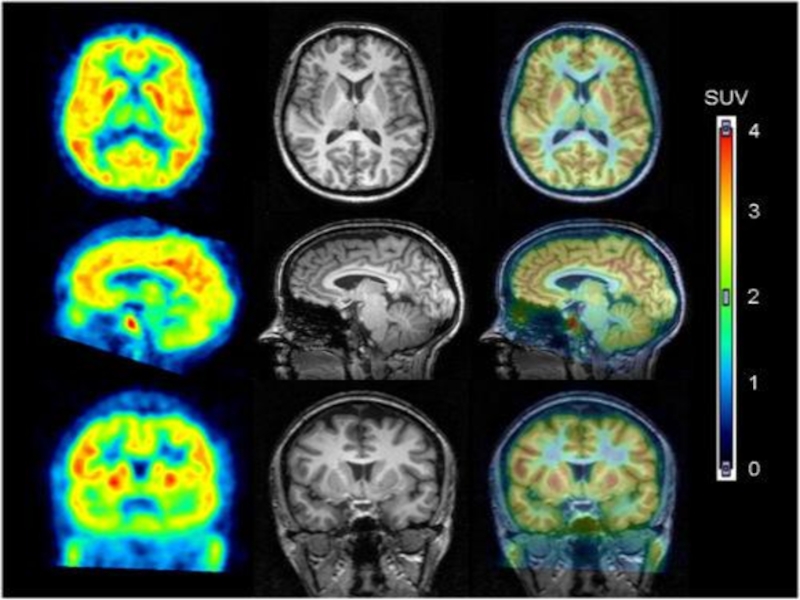

В настоящее время в

наиболее оснащенных зарубежных медицинских центрах большую часть ПЭТ исследований выполняют

на приборах, в которых в одном модуле объединены ПЭТ и КТ или МРТ сканеры и оба вида исследований выполняются одновременно. Комбинация ПЭТ/КТ/МРТ сканеров позволяет получать изображения, на которые точно определяется местоположение нарушений метаболизма в организме. ПЭТ/КТ/МРТ─ гибридная технология, сочетающая функциональную и структурную нейровизуализацию. При этом КТ и МРТ сканирования дают точное представление об анатомических особенностях головного мозга, а ПЭТ-сканирование обеспечивает информацию о его функционировании. Комбинация нескольких методов нейровизулизации обеспечивает возможность более точной диагностики, чем КТ, МРТ или ПЭТ исследования по отдельности.

В настоящее время в наиболее оснащенных зарубежных медицинских центрах большую часть ПЭТ